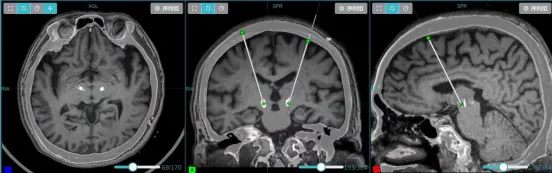

术后复查CT与术前规划影像融合比对显示,DBS电极植入位置与双靶点完全吻合,手术精准度达到预期。患者生命体征平稳,无出血、感染等并发症,肢体活动如常,微毁损效应显现,肢体僵硬缓解。

640 (1)_副本

▲ 薄层MRI和CT融合重建 ,显示电极完美精准植入